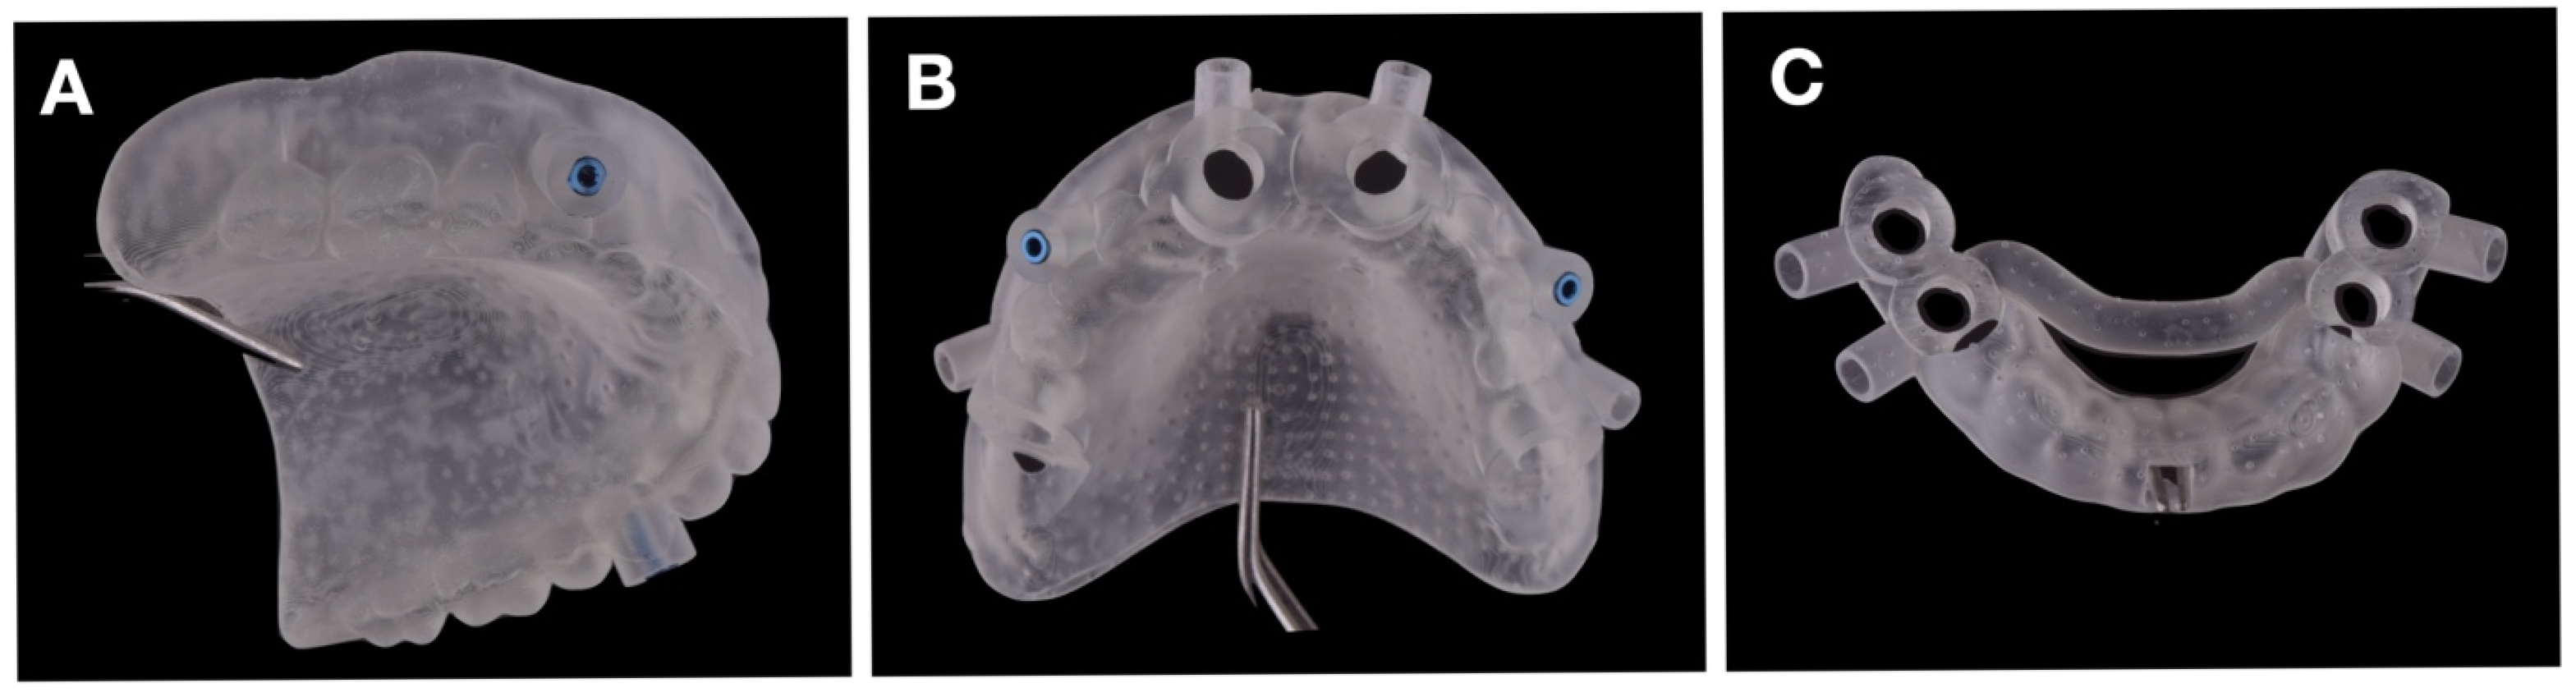

After completing the implant planning and fixation pins positioning in Implastation Version 5.3.2. (ProDigiDent, Batavia, IL, USA), the digital files were exported in STL format. For the maxilla, two separate guides were created: (i) a pin-drilling stabilization guide duplicated from the maxillary denture and positioned in perfect occlusion (Figure 5A), and (ii) the main guide for implant insertion (Figure 5B). For the mandible, a single, tooth-supported, sleeveless guide was designed (Figure 5C).

Figure 7 shows photographs of the 3D-printed surgical templates. To assess clinical readiness, we test-fitted all guides on printed jaw models to confirm passive seating and occlusal stability. Pre-operative bench tests documented a passive fit within <100 µm, allowing safe transition to surgery.

The maxillary workflow utilized two guides (a fixation pin insertion guide and an implant site preparation guide with internal cooling), whereas the mandibular workflow employed a single, tooth-supported implant bed osteotomy guide with internal cooling (Figure 7A–C).

Figure 5. Design of surgical guides without internal cooling channels: (A) guide for drilling the positioning pin locations of the maxillary guide; (B) maxillary surgical guide; (C) mandibular surgical guide.

Figure 7. Three-dimensional-printed surgical templates used in this study: (A) guide for drilling the holes for the insertion of fixation pins; (B) maxillary surgical guide; (C) mandibular surgical guide.